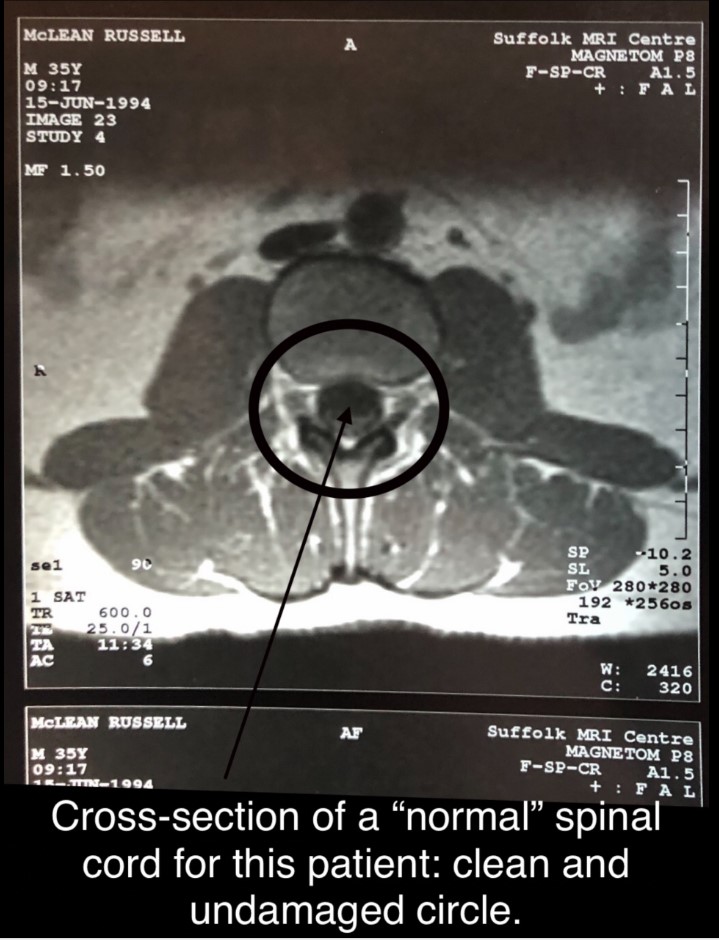

That reason was because of spinal injury sustained whilst on duty:-

1]. Assisting a waterlogged casualty out of the sea at Campbeltown Harbour. Unfortunately it was shortly after midnight and no backup emergency service officers were available to assist. That was the first spinal injury. Crucially the casualty survived.